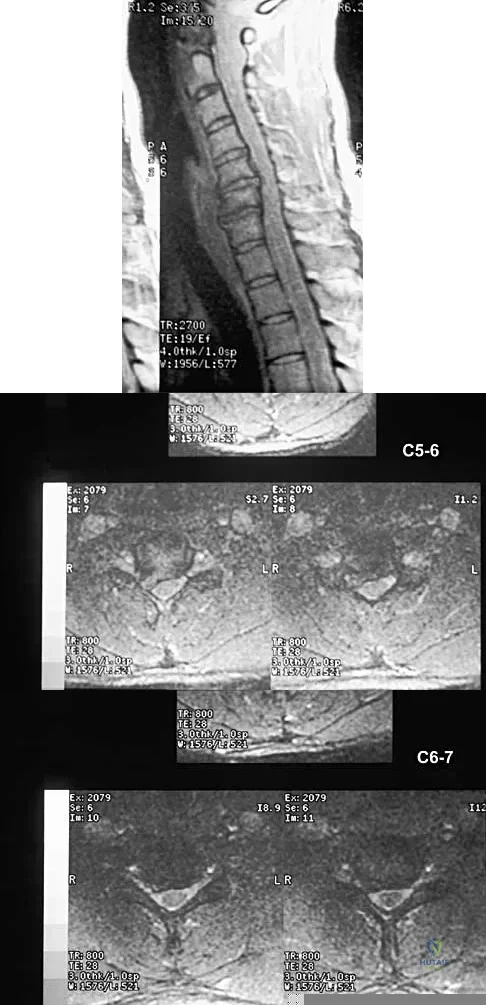

A 40-year-old carpenter has a 3-month history of right arm pain and neck pain that now leaves him unable to work. Examination reveals a positive Spurling test, weakness of the biceps, and a mildly positive Hoffman's sign on the right side. Electromyography and nerve conduction velocity studies show a right C6 deficit. Figures 27a through 27c show MRI scans that reveal two-level spondylotic disease at C5-6 and C6-7, a large herniated nucleus pulposus at C5-6, and a prominent ridge and hard disk at C6-7. Nonsurgical management fails to provide relief, so the patient elects surgical intervention. Which of the following surgical options would give the best long-term results?

Explanation